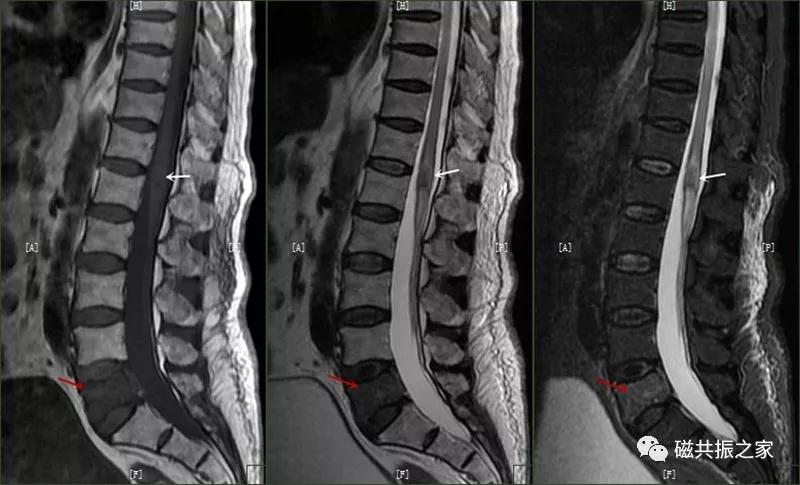

8.椎体骨折

椎体压缩性骨折常成前窄后宽的楔形改变,新鲜骨折(红箭头)常在T1WI呈低信号(出血时可呈高信号),T2WI呈低、中信号,在脂肪抑制的T2WI上呈高信号。椎体陈旧性骨折(白箭头)信号类似于正常椎体信号。如需了解脊柱骨折分型请查阅脊柱骨折的分型。